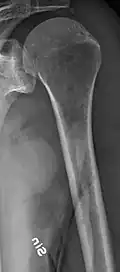

The diagnostic examination of a person with suspected multiple myeloma typically includes a skeletal survey. This is a series of X-rays of the skull, axial skeleton, and proximal long bones. Myeloma activity sometimes appears as "lytic lesions" (with local disappearance of normal bone due to resorption) or as "punched-out lesions" on the skull X-ray ("raindrop skull"). Lesions may also be sclerotic, which is seen as radiodense.[76] Overall, the radiodensity of myeloma is between −30 and 120 Hounsfield units (HU).[77] Magnetic resonance imaging is more sensitive than simple X-rays in the detection of lytic lesions. An MRI may supersede a skeletal survey, especially when vertebral disease is suspected. Occasionally, a CT scan is performed to measure the size of soft-tissue plasmacytomas. Nuclear Medicine Bone scans are typically not of any additional value in the workup of people with myeloma (no new bone formation; lytic lesions not well visualized on nuclear bone scan).

Multiple myeloma in the upper arm -